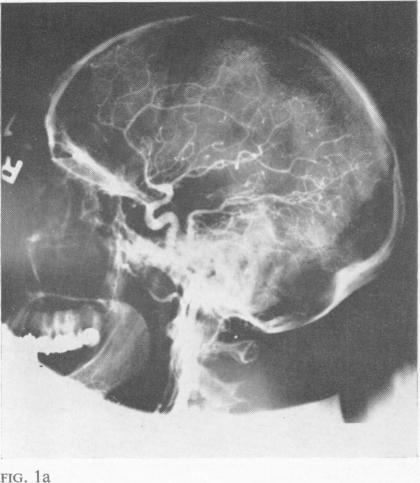

Blain J G, Logothetis J

J Neurol Neurosurg Psychiatry. 1966 Aug;29(4):346-9. doi: 10.1136/jnnp.29.4.346.